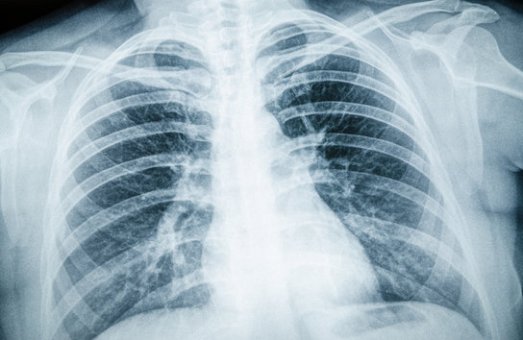

Рентгендіагностика — це сукупність методів обстеження, які ґрунтуються на використанні рентгенівських променів. Вони дозволяють отримати чіткі зображення кісток і суглобів, органів грудної клітки (серця та легень),шлунково-кишкового тракту, сечовидільної системи, судин та молочних залоз. Сучасні цифрові технології, які застосовуються у лікарні ім. Мечникова, забезпечують високу якість результатів при мінімальному променевому навантаженні.

Флюорографія та рентген грудної клітки допомагають виявити пневмонію, туберкульоз, пухлини.

Знімки показують запальні процеси, пухлини, зміни серця й легенів.